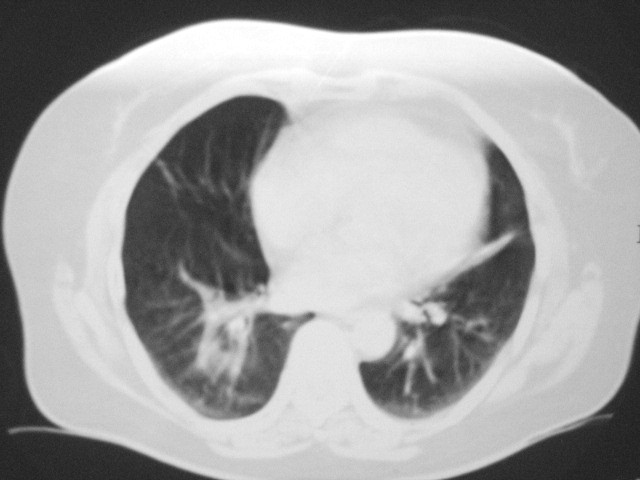

以下是引用清清楚楚在2007-8-28 7:13:00的发言:[br]右肺下叶可见斑片状高密度影,边缘模糊;右肺中叶内侧段及左肺舌段亦可见小斑片状模糊影。[br]考虑双肺感染,建议抗炎治疗后复查。

以下是引用天南地北在2007-8-27 23:49:00的发言:[br]右肺下叶可见斑片状高密度影,边缘模糊;右肺中叶内侧段及左肺舌段亦可见小斑片状模糊影。[br]考虑双肺感染,建议积极抗炎治疗后复查。

以下是引用天南地北在2007-8-27 23:49:00的发言:[br]右肺下叶可见斑片状高密度影,边缘模糊;右肺中叶内侧段及左肺舌段亦可见小斑片状模糊影。[br]考虑双肺感染,建议抗炎治疗后复查。

以下是引用难听在2007-8-28 13:17:00的发言:[br]右肺下叶背段支气管狭窄,是否可以考虑新生物伴阻塞性肺炎.请大家帮帮忙,这个病人是卫生局长的丈母娘.惹不起啊.